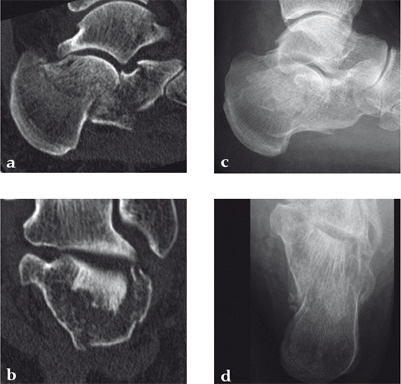

Case 1: A 70-year-old man sustained a Sanders IIA fracture of his left calcaneus.

(Case provided by Michiel Verhofstad, Tilburg, The Netherlands)

After open reduction a gap was left due to impaction of the osteoporotic metaphyseal bone. To support preliminary maintenance of the primary reduction a block of calcium phosphate was introduced beneath the posterior facet. The rest of the gap was filled with Norian drillable. After hardening plate osteosynthesis was performed. Two screws were placed through the fiber-enhanced calcium phosphate. Weight bearing was started 6 weeks later. After 6 months the fracture was healed without secondary loss of reduction. Note that at that time the degradation of the void filler is visible.